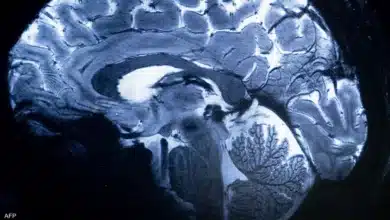

ماذا تفعل قلة النوم في دماغك؟.. شيء لا يصدق

لن تصدق.. ماذا يفعل مخك في نفسه وأنت نائم؟

نومك قد يكون قاتـ.ـلاً.. كيف يؤثر نقص النوم على صحتك؟

قلة النوم أخطر مما تعتقد وهذا ما تسببه للجسم